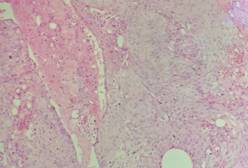

经家属同意后,医生决定栓塞肿瘤近端的供血动脉,并于当天行左侧中颅窝占位病变切除术;术中可见肿瘤灰红色,有假包膜,分块切除肿瘤;由于术前行介入栓塞,术中可见血供明显减少,且出血少,左侧大脑中动脉及左侧大脑前动脉被肿瘤压迫移位,医生给予保护后将肿瘤全切除。术后黄女士恢复顺利,已痊愈出院。病理结果显示:脑膜瘤,合体细胞型,WHO I级。

术后病理:“左侧蝶骨嵴”脑膜瘤,合体细胞型,WHO Ⅰ级